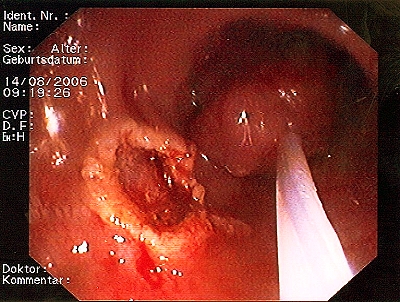

Polypabtragungsstelle

Gut sichtbarer Blutstrahl nach Abtragung eines Polypen

Sichere Blutstillung durch einen Metallclip